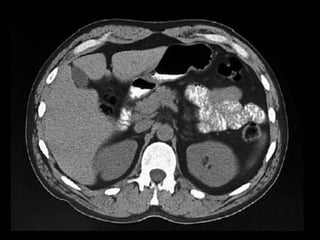

Coleções líquidas agudas

Ocorrem em cerca de 40% dos casos;

Podem ser em torno da glândula ou extra-

pancreático;

Carecem de cápsula e são confinadas ao espaço

anatômico onde se encontram;

Podem dissecar para outros locais: mediastino,

pararrenal posterior, órgãos sólidos ou parede de

alça intestinal.

Coleções líquidas agudas- TC

Hipodensas

Mal definidas

Sem cápsula ou parede reconhecível

Resolução espontânea em 50% dos casos;

Complicações: dor, infecção secundária e

hemorragia;

São passíveis de drenagem percutânea caso não

regridam ou se tornem infectadas.